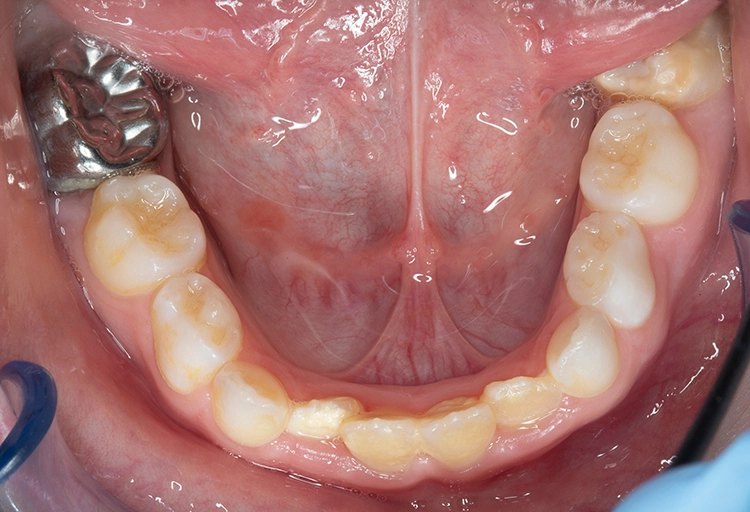

Fissurenversiegelung

Bekes/BoukhobzaAbb. 2: Fissurenversiegelung an Zahn 36 mit umschriebenen Opazitäten.

Fissurenversiegelungen können bei MIH-Molaren generell dann durchgeführt werden, wenn diese keine posteruptiven Schmelzeinbrüche im okklusalen Bereich aufweisen und nicht kariös kavitiert sind [7] (Abb. 2). Es empfiehlt sich, vor der Applikation des Versiegelungsmaterials ein Adhäsiv anzuwenden, um den Verbund zum porösen, mindermineralisierten Schmelz zu verbessern [8–10]. Sollte der Zahn noch nicht vollständig eruptiert sein, kann auch ein niedrigvisköser Glasionomerzement zum Einsatz kommen.